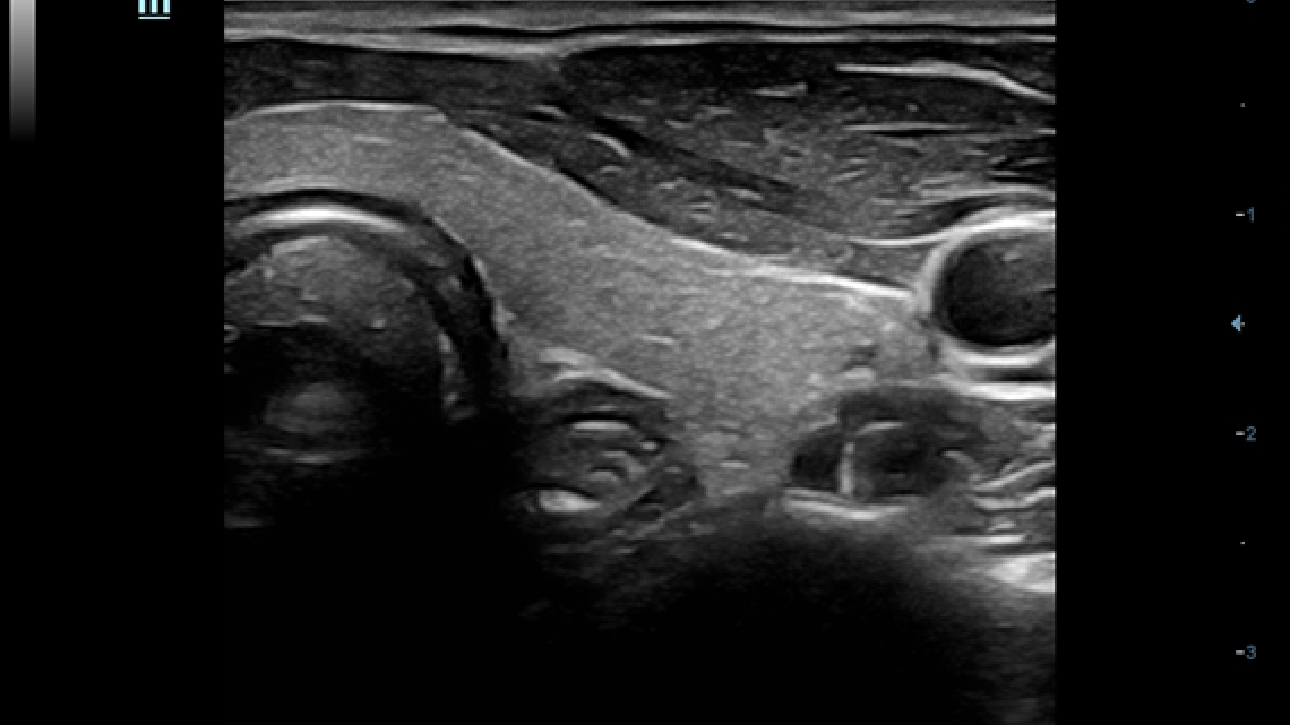

X-Insight es la soluci├│n intuitiva para una mejor visualizaci├│n.

La nueva soluci├│n de Mindray es una excelente transformaci├│n desde la continua comprensi├│n de las necesidades cl├Łnicas del usuario, combinada con la evoluci├│n de la tecnolog├Ła de los ultrasonidos m├Īs puntera. Repleto de vitalidad, con el ├║nico objetivo de visualizar el futuro y evitar los l├Łmites, el ec├│grafo DC-60Exp con X-Insight est├Ī constantemente mejorando con una escalabilidad aumentada. Como un socio personal, el equipo de ultrasonidos DC-60 Exp con X-Insight se centra en lo que verdaderamente importa, ayudando al usuario a administrar su pr├Īctica cl├Łnica con facilidad y seguridad.

Bas├Īndose en una profunda comprensi├│n de las necesidades del usuario, el sistema de ultrasonidos DC-60 Exp con X-Insight est├Ī dise?ado para ofrecer una alta eficiencia con im├Īgenes de precisi├│n, la cual se ve potenciada por una claridad inmediata, una inteligencia excepcional y benefici├Īndose de una c├│moda experiencia.